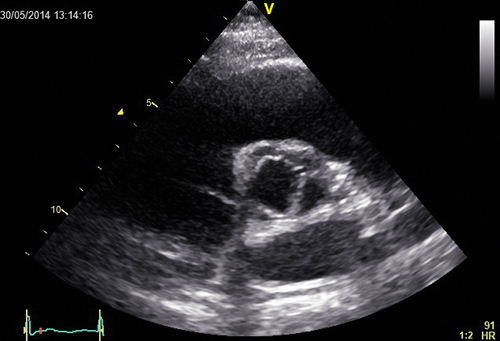

Fallbeskrivning